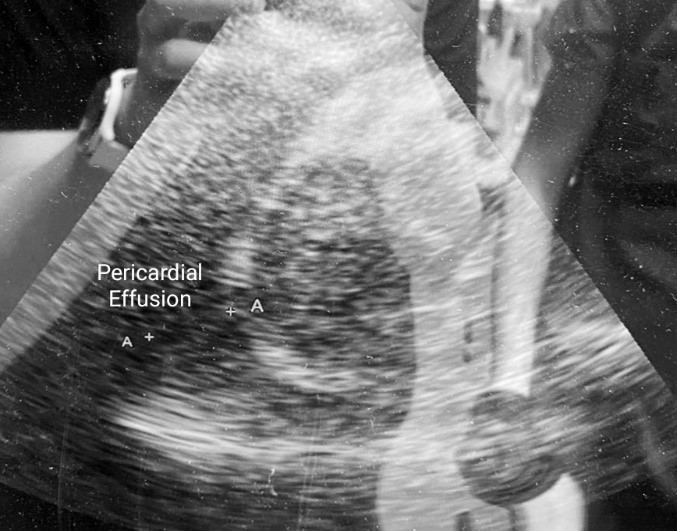

The most significant condition with a life-threatening property that must not be missed when performing POCUS, is pericardial tamponade. “The surroundings” refers to pericardium and the structures around the heart whose pathologic conditions could lead to impaired hemodynamics. Accumulation of free fluid between the two pericardial layers could be detected in all cardiac windows where pericardial effusion will be visualized as a dark anechoic area around the heart whose dimensions could vary depending on the amount of pericardial fluid [8]. In emergent cases where time to treatment is crucial, even only subcostal examination could reveal presence of pericardial effusion with or without hemodynamic compromise leading to fast treatment decision. If the anechoic dark space could be seen in all windows around the heart, then the pericardial effusion is probably big. Essential when deciding if pericardiocentesis is needed or not, is the presence or absence of hemodynamic compromise which by echocardiographic could be identified by detecting collapse of the right atrium in systole or right ventricular collapse in diastole. Right heart collapse could be identified when using subcostal or apical 4-chamber view during the examination where inward movement of the right ventricular free wall is met during diastole. Pericardial tamponade in 92% of the cases is accompanied with dilation of the IVC [8] which becomes larger than 2.5cm and non-collapsible implying impaired anterograde blood flow and should be seen and assessed in subcostal view as it was explained earlier in this article.

Figures 2 & 3. Pericardial Effusion surrounding the heart.